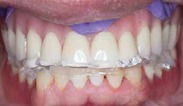

Step 4: Virtual Prosthetic Planning

Virtual prosthetic planning is a critical step in the digital workflow for edentulous patients, ensuring that implant placement is guided by prosthetic requirements rather than solely by bone availability. This prosthetic-driven implant planning approach integrates digital dentures as a reference, optimizing both function and esthetics.

Prosthetic-Driven Implant Planning

In traditional implant planning, the focus was primarily on bone availability, often leading to implants being placed in non-ideal positions for prosthetic function. Prosthetic-driven planning, however, reverses the process, starting with the ideal prosthetic outcome and then determining implant placement accordingly.